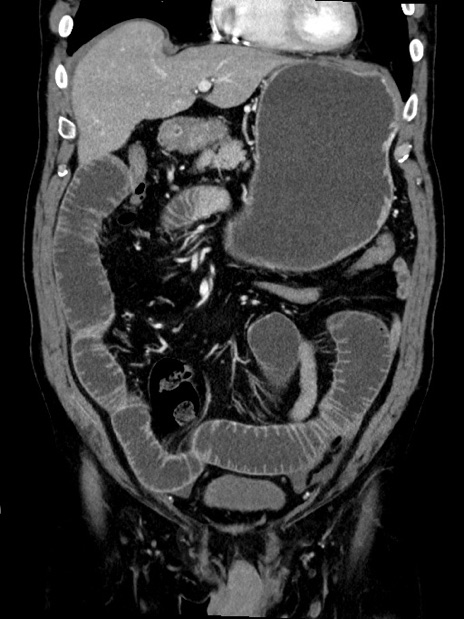

症例35(冠状断像)

【症例】70歳代 男性

【主訴】腹部膨満、嘔吐

【現病歴】昨日より腹部膨満感出現。本日増悪し、仙痛出現。嘔吐あり、受診。

【既往歴】糖尿病、胆摘後

【身体所見】BP 149/80mmHg、HR 74/min、BT 35.9℃、腹部:膨満、軟、圧痛なし。腸雑音減弱あり。上腹部正中切開瘢痕あり。

【データ】WBC 13500、CRP 1.72